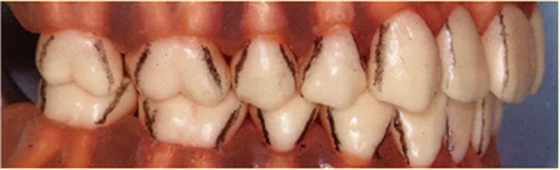

4点法和6点法都是将牙齿分区进行检测的,但是牙齿本身是没有分界线的。

(如下图所示,在脑中要有牙齿转角处的线条印象。将拐角处的线条延伸至牙颈部纪委各区分界线。)